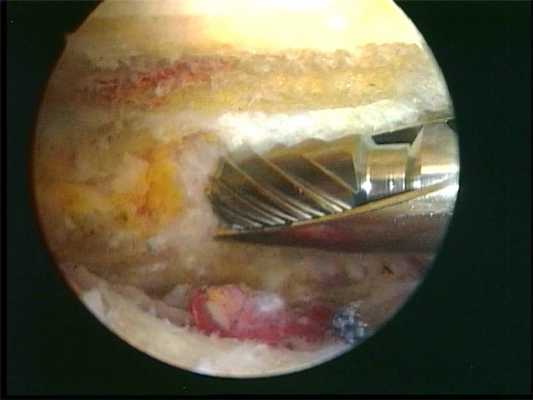

Безрезультатность консервативной терапии может привести к потребности хирургического удаления кальцификатов, что может быть выполнено как открытым методом, так и артроскопически. В большинстве случаев проводится артроскопическая операция. Артроскоп вводится в полость сустава через миниатюрный разрез. При этом изображение содержимого плечевого сустава отображается на экране видеодисплея. При осмотре сустава хирург обнаруживает отложения кальция и удаляет их при помощи специальных инструментов.

артроскопическая картина кальцификата, подвергающегося обработке шейвером